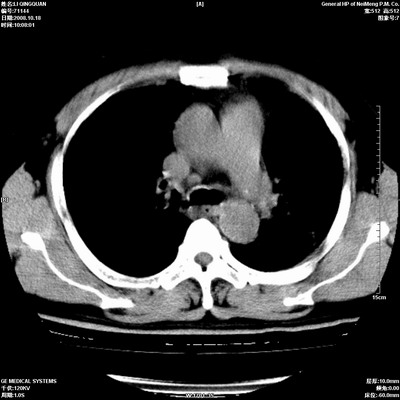

以下是引用duguo在2008-10-19 13:59:00的发言:[br]左肺上叶支气管狭窄,首先考虑中心型肺癌伴阻塞性肺炎\\肺不张.

以下是引用ybing在2008-10-19 12:58:00的发言:[br]左肺上叶阻塞性炎症-建议支气管镜进一步检查除外中央型肺癌

以下是引用随光逐影在2008-10-19 14:31:00的发言:[br]考虑左肺中央型肺癌并左肺上叶阻塞性肺炎,肺不张。